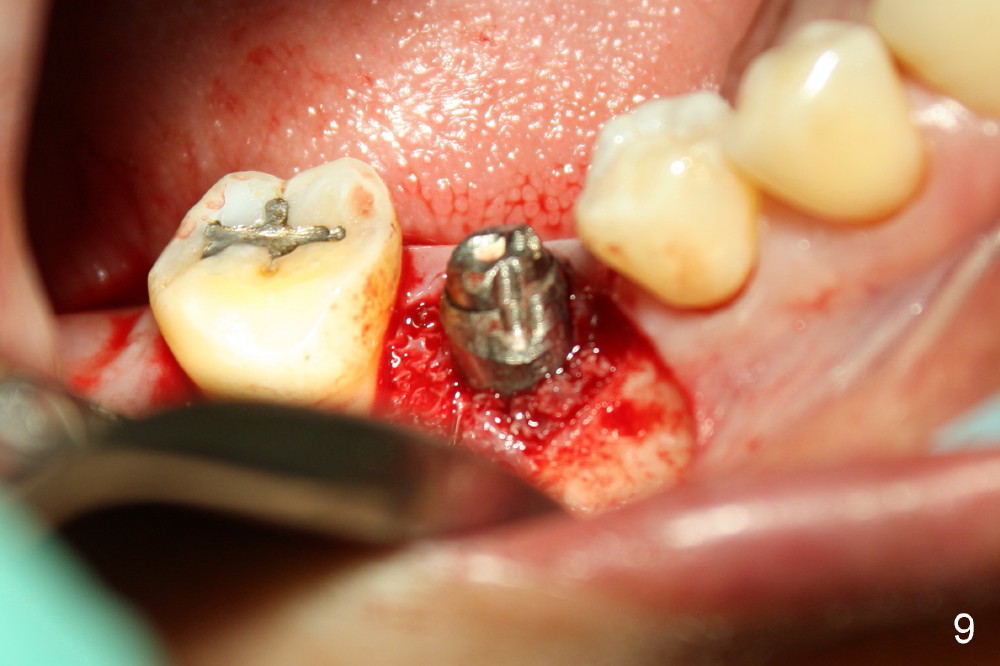

The infection may be related to chronic infection at the tooth #9. The latter is extracted, but the infection at the site of #30 does not resolve (Fig.5,6). The buccal flap is raised to reveal granulation tissue distobuccal to the implant (Fig.7). Bony defect and implant thread exposure are shown after debridement (Fig.8). Irradiated cancellous bone graft is placed to the defect (Fig. 9, Rocky Mountain Tissue Bank). The flap is closed with relative tension free. The definitive crown is temporarily cemented. The graft is exposed with no infection 2 week post grafting (Fig.10). The distobuccal defect appears to have healed 5 months post grafting (Fig.11) and the crown is permanently cemented (Fig.12). There is no buccal bone resorption, probably associated with immediate implantation. The patient remains asymptomatic 13 months postop.